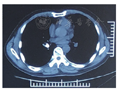

男性患者,55岁,因上颌后牙拔除后3个月,要求种植修复于2017年3月济南军区总医院口腔科就诊。口内检查情况为26、27缺失,拟在26、27位点植入两枚4.8 mm×10.0 mm种植体。手术开始后,患者咽反射明显,不停要求吸出口内分泌物,吸引器吸引时又出现恶心咳嗽,立即停止手术,与患者沟通后认为患者尚可耐受手术,休息后患者状态良好,采取改变椅位角度、在咽部放置纱布等措施进行保护,旋入27种植体愈合基台时纱布影响操作,遂取出纱布在旋紧27种植体愈合基台完成后,患者突然剧烈咳嗽闭合口唇,螺丝刀掉落口内并被吞入。放平患者后进行椅旁X线照射,示螺丝刀位于主支气管内,患者咳嗽但无呼吸不畅。胸部CT可见螺丝刀位于右侧主支气管内(图1,图2),六方刀口朝上,利于纤维支气管镜取出。呼吸内科医师在充分麻醉下,使用电子纤维支气管镜异物夹持器械(软管)取出异物(图3)。患者无咳嗽,常规口服三日抗生素(阿莫西林、甲硝唑)预防肺部感染。

(3)异物位置、症状:误吸的异物大部分位于右主支气管,其次是左主支气管、右肺,几乎没有异物掉落至左肺的病例报道[3]。发生误吸的患者可能出现咳嗽,仅有1例报道出现疼痛,1例恶心,但大部分报道病例症状不明显。仅凭症状很难判断异物位置,需借助影像学手段明确诊断[3]。